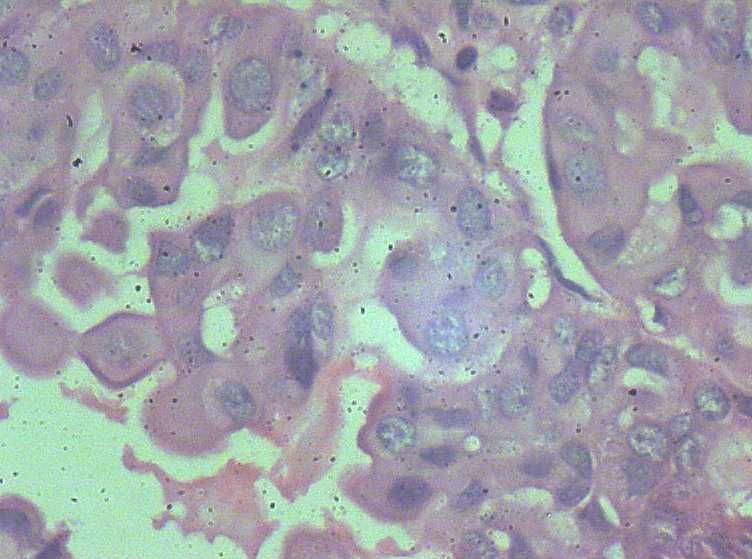

女,27岁,剖宫产术中见一侧卵巢一肿物。大体:椭圆形肿物大小3*2*1.5表面光滑,剖开内容为浅黄色胶状物,质均,囊内壁较光滑,部分见细小乳结构。